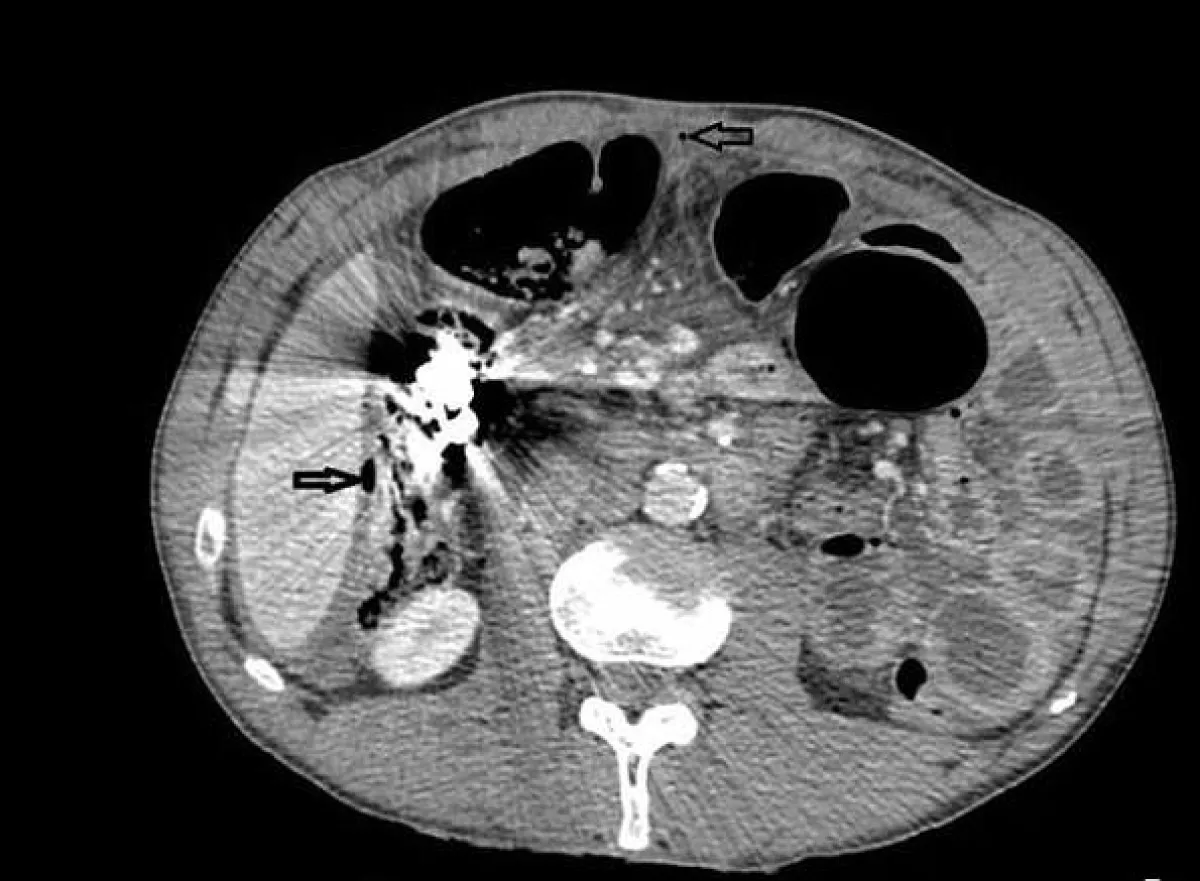

وتم نقل المريض إلى الطوارئ مرات عدة، وخضع لـعمليات على مدى 5 سنوات، لأنه كان يتقيّأ دمًا ويتعرض لألم شديد، نتيجة وجود هذه الكتل في بطنه. وأُجريت له خمس عمليات لإزالة المسامير والسكاكين، والمكسرات، ورأس مفك البراغي، بالإضافة إلى مقابض المعالق والحصى، وأسلاك الحديد والعملات المعدنية، من بطنه.

وكان الرجل قد ذهب إلى المستشفى لأول مرة، في مايو 2012، وفقًا لـ"الديلي ميل"، حيث ظهرت لديه علامات انسداد مخرج المعدة، ما دفع الأطباء لإزالة البازهر عبر التنظير.

وبعد 8 أشهر، نُقل المريض إلى المستشفى للسبب نفسه، ثم خضع للجراحة، حيث وجد الأطباء آثارًا للمسامير والسكاكين، والأدوات الحادة الأخرى في بطنه.